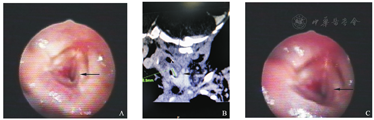

入院查体:T 37 ℃,P 131次/min,R 61次/min,神志清楚,精神反应尚可。口周无发绀。喉鸣明显,呼吸急促,三凹征阳性,双肺可闻及痰鸣音。心腹可。右侧腹部可见一绿豆大小鲜红色肿物,边界清楚,压之变淡。血气分析:pH 7.284,PCO2 63.3 mmHg,PO2 50 mmHg,HCO3- 30 mmol/L,BE 3 mmol/L,Na+ 135 mmol/L,K+ 4.7 mmol/L,Ca2+ 1.45 mmol/L。红细胞压积21%,Hb 7.1 g/dl。腹部彩超:肝内多发低回声病变(血管瘤?),肝内多个低回声团块,大者约2.7 cm×2.6 cm,边界清,探及血流信号。纤维支气管镜检查:紧邻左侧声带声门下侧壁可见一直径约1 cm紫红色团状物,向管腔内凸出,并声门下狭窄。左侧壁声门下肿物待查:声门下血管瘤?(图2A)。颈部平扫+增强CT:左颈部气管与左侧甲状腺之间见不规则软组织密度影,最大截面积约为8.2 mm×3.8 mm,长约8.8 mm,上至声门下区,下至甲状腺峡部水平,与周围组织分界不清,增强动脉期均匀强化,静脉期及延迟期强化更为明显,边界清晰,呈弧形包绕左侧气管壁,局部气管狭窄。左颈部富血供占位性病变,考虑来源于气管管壁血管源性肿瘤,血管瘤?(图2B)。

A.治疗前支气管镜所见;B.颈部CTA;C.治疗后支气管镜下所见。

入院诊断:声门下血管瘤并皮肤血管瘤并肝内多发血管瘤。入院予CPAP辅助呼吸,抗感染,布地奈德雾化混悬液+特布他林雾化等治疗,第3天开始口服普萘洛尔,第6天气促缓解,喉鸣明显减轻,改鼻导管给氧,第10天患儿呼吸平稳,喉鸣消失,停止吸氧,第11天复查腹部彩超:肝内多发低回声病变(血管瘤?),肝内多个低回声团块,大者约2.2 cm×2.1 cm,气管上段左侧壁(环状软骨下方)探及一等回声团块大小约0.8 cm×0.7 cm,通气的气管腔气体回声较上次增多。第12天复查支气管镜:紧邻左侧声带声门下侧壁可见一直径约0.9 cm紫红色团状物,较前略缩小,声门下通气较前改善(图2C)。第13天患儿少许喉鸣,呼吸平稳,肺部未闻及啰音,右侧腹部绿豆大小肿物颜色变为暗红色,生命体征平稳,出院并继续抗血管瘤治疗,随访中。